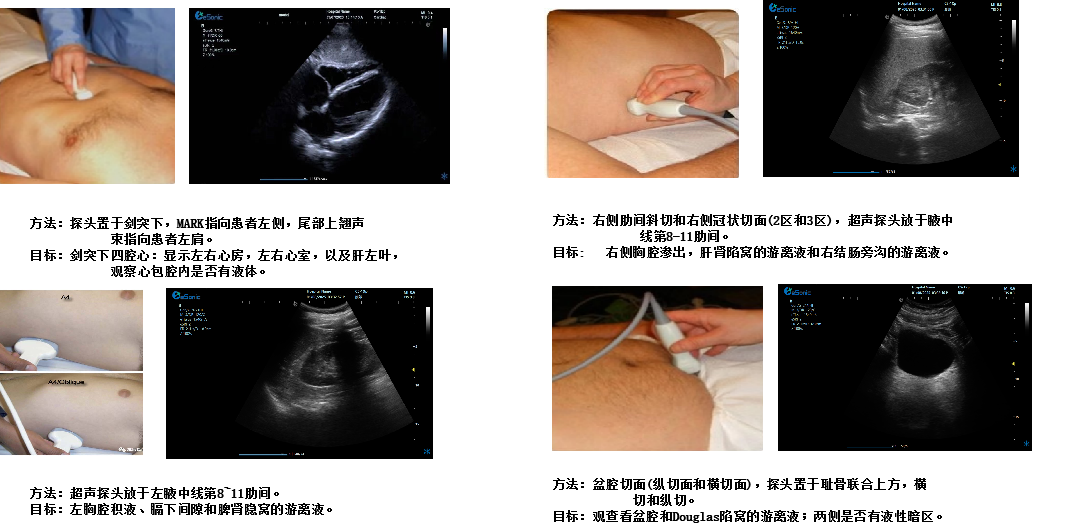

创伤评估FAST

image.png

重症心脏超声- FATE方案:

是重症病人循环管理推荐的目标导向超声评估评估方案之一,在此基础上扩展快速的下腔静脉超声检查,增加和完善容量状态和液体反应性的评估。